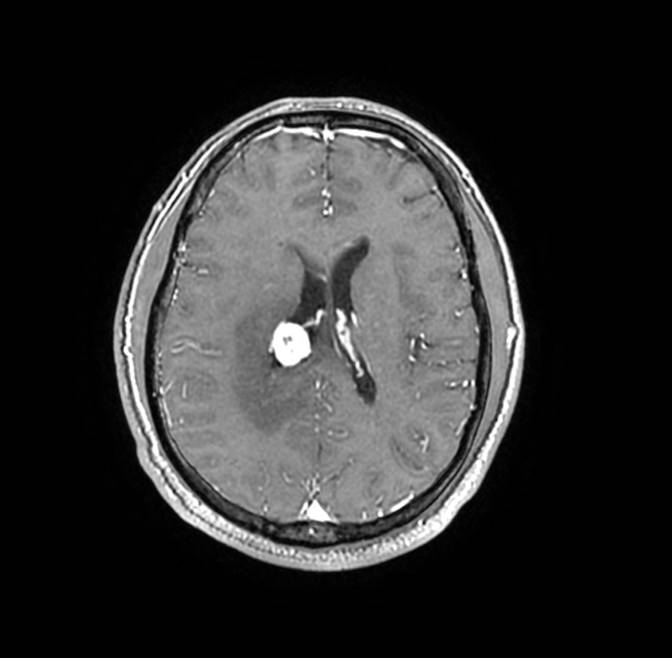

磁共振影像圖

圖1

圖2

圖3

圖4

MR診斷:右側(cè)側(cè)腦室三角區(qū)及側(cè)腦室旁占位,考慮惡性腫瘤可能,間變型腦膜瘤?轉(zhuǎn)移瘤?

MR鑒別診斷

常規(guī)MR檢查是診斷腦膜瘤的有效手段,可以明確腫瘤發(fā)生的部位、形態(tài)和數(shù)目等特征以及病變向鄰近腦實質(zhì)侵犯的程度和范圍,典型腦膜瘤呈等或(和)稍長T1、等或(和)稍長T2信號,??娠@示完整的包膜,增強掃描因腫瘤內(nèi)部新生血管通透性不同呈不同程度強化,由于腫瘤組織的強化程度與腫瘤的惡性程度不完全一致,導致MR常規(guī)檢查在腦膜瘤分級分型方面仍存在一定的困難。擴散加權成像( diffusion weighted imaging,DWI) 及表觀擴散系數(shù)( apparent diffusion coefficient,ADC) 被廣泛用于腦腫瘤的分級、分子分型和腫瘤侵襲性預測,并取得了良好的性能。目前,對于非典型腦膜瘤腦實質(zhì)侵犯的診斷的金標準依賴于組織病理學。